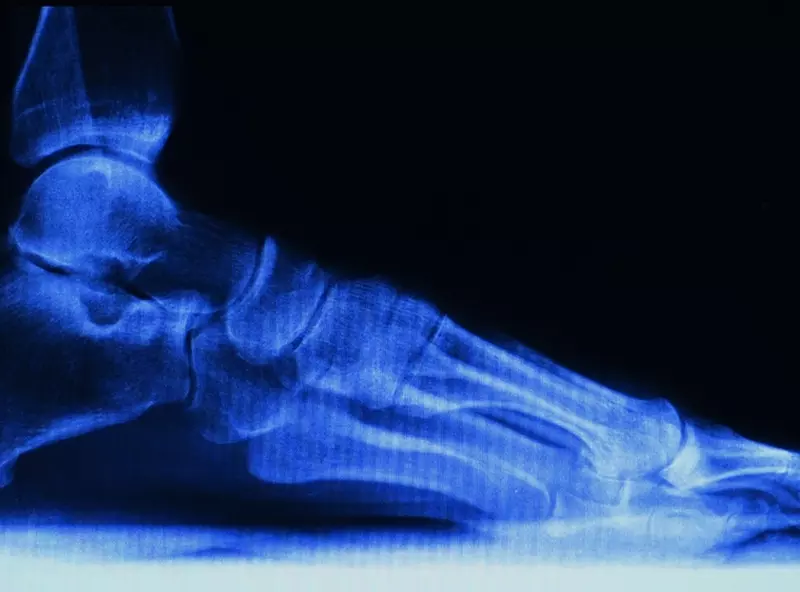

Deformacja Haglunda jest wyniosłością kostną występującą na tylno-górnym biegunie kości piętowej [1, 2, 4, 5]. W tym obszarze znajdują się ważne struktury, takie jak kaletka powierzchowna i głęboka ścięgna Achillesa oraz przyczep tego ścięgna.

Ścięgno Achillesa jest największym i najsilniejszym ścięgnem w ciele człowieka [1]. Przyczep ścięgna Achillesa do kości piętowej ma powierzchnię 1 x 2 cm i znajduje się ok. 2 cm poniżej tylno-górnej krawędzi guzowatości kości piętowej. Tylną powierzchnię kości piętowej można podzielić na trzy obszary. Górna jedna trzecia kości piętowej jest trójkątna z wierzchołkiem górnym. Na jej powierzchni znajduje się kaletka głęboka ścięgna piętowego. Ścięgno Achillesa przyczepia się do pokrytej bruzdami środkowej i dolnej jednej trzeciej kości piętowej. W dolnej jednej trzeciej przeplatają się włókna rozcięgna podeszwowego i ścięgna Achillesa [1, 6]. Włókna ścięgna piętowego skręcają się o mniej więcej 90°, włókna przyśrodkowe przechodzą na stronę boczną, przyczepiając się do kości piętowej, a włókna boczne przechodzą na stronę przyśrodkową [1].

Kaletka głęboka ścięgna piętowego z przodu jest ograniczona przez poduszkę tłuszczową, z tyłu – przez ścięgno Achillesa. Jest ona zgniatana podczas wyprostu w stawie skokowym przez ścięgno Achillesa zbliżające się do osi obrotu w stawie. Jej główną funkcją jest stworzenie odstępu między ścięgnem Achillesa a osią stawu. Oprócz kaletki głębokiej w tym obszarze występuje też kaletka powierzchowna, znajdująca się między ścięgnem a skórą.